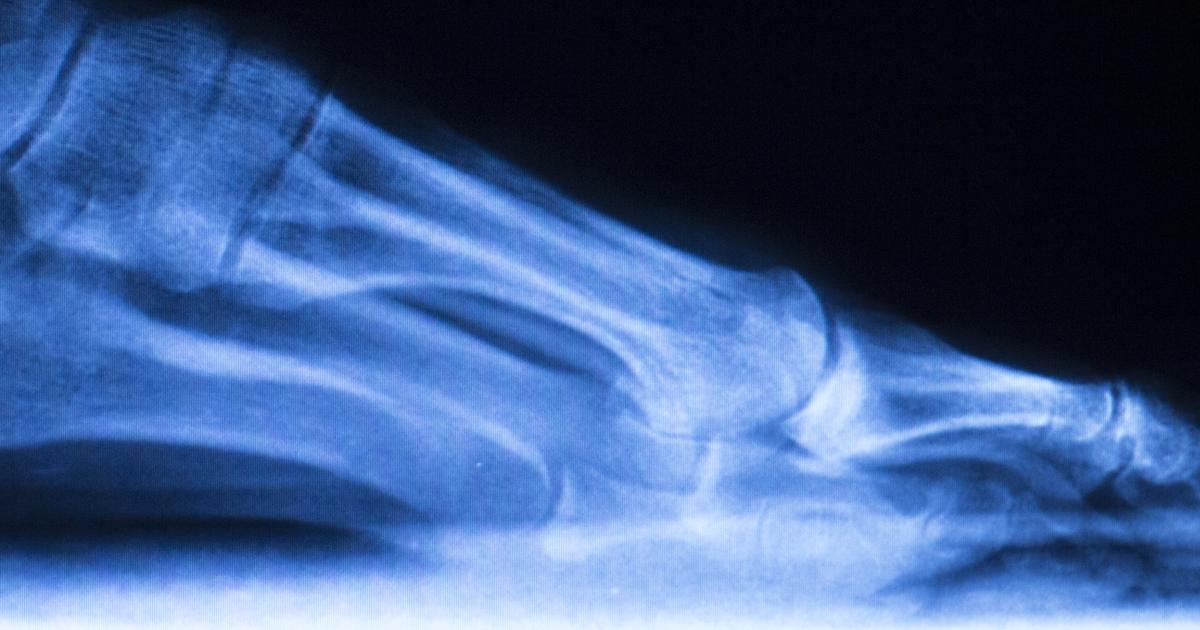

An individual can develop Charcot foot when they have an incorrectly treated broken foot or ankle. When an individual injures their foot or ankle and suspects a bone could be broken or fractured, they typically go to a provider for medical diagnosis. Bone breaks and fractures can be detected by diagnostic imaging tests such as a bone scan, CT scan, MRI, and x-rays. Depending on the severity and location of the break or fracture, the patient may require surgery to realign the bone. With or without surgery, the affected individual will be placed in a cast for immobilization for at least six weeks to allow the bone to grow back together. However, some patients who become injured in the foot or ankle mistake a break for a minor sprain or strain, or they are not aware of the injury at all. This situation can happen in individuals who have nerve problems that compromise the pain sensation in their foot. Instead of getting proper treatment for the break or fracture, the patient continues walking and standing on the foot and ankle. Bone fractures and breaks are common in individuals who have sensation loss in the foot and ankle because their neuropathy causes balance issues and immobility that stimulate changes in the balance of bone production and breakdown. This imbalance causes bone loss and weakness, increasing the risk of suffering a fracture.